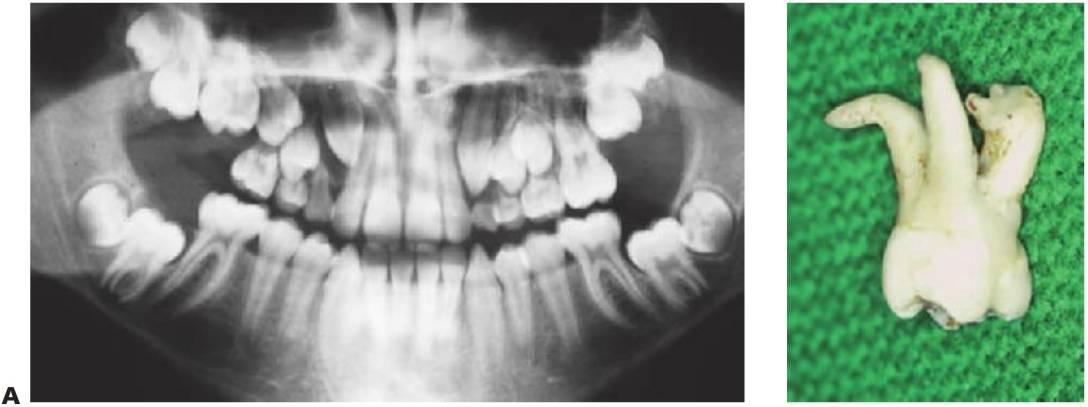

Odontomas

Los odontomas se producen debido a una alteración de la diferenciación, y suelen presentarse debido a la falta de erupción de un diente permanente. En los odontomas compuestos se encuentran masas de dentículos irregulares en un estroma de tejido blando circunscrito. Los odontomas complejos son alteraciones de tipo desorganizado, con una masa aislada e incidental de tejido calcificado que contiene todos los elementos dentales. Un diente de la serie normal puede sustituirse por un complemento dental normal o bien por un odontoma (fig. 9.12).

Tratamiento

- Enucleación.

- Dependiendo de la duración del diagnóstico, los dientes permanentes pueden quedar en una posición ectópica y pueden requerir exposición quirúrgica y alineación ortodóncica.